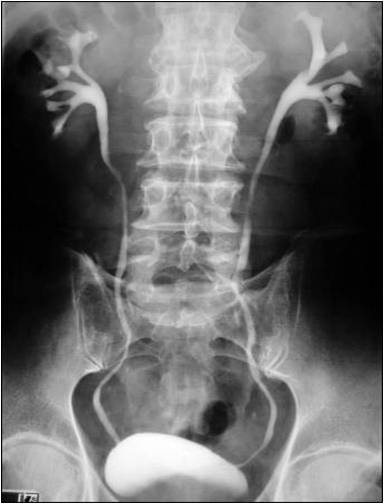

Рентгенологические методы

Рентгенологические исследования давно и прочно обосновались в медицинской практике. Используются они и для диагностики пиелонефрита. На обзорном снимке брюшной полости контуры почек едва различимы. Для получения более информативной картины используется контрастное вещество, хорошо отражающее рентгеновские лучи. Чтобы доставить его в почки, применяется довольно простой способ. Препарат хорошо проходит из кровотока через почечный фильтр и оказывается в моче. Поэтому незадолго до проведения исследования вещество вводят в организм посредством обычной внутривенной инъекции.

Период существования препарата в крови строго определён. По истечении этого временного промежутка делается несколько снимков почек с разным интервалом. Их последующее изучение позволит установить характер движения мочи, форму чашек, лоханок и мочеточников, диагностировать наличие некоторых видов камней. Это исследование носит название экскреторной урографии.

При экскреторной урографии можно получить хорошее изображение мочевыводящих путей